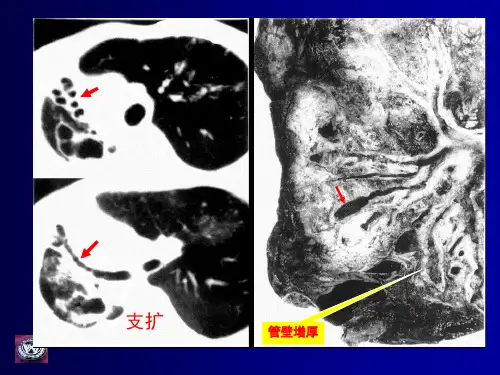

31、印戒征(支气管轨道征):

是支气管扩张的影像表现,分为柱状、串珠状、囊状扩张。

是支气管壁弹性组织和肌肉组织破坏导致的局部支气管不可恢复的异常扩张,是受累支气管多种病理过程共同的最终结果,支扩病理改变是管腔扩张和管壁增厚。